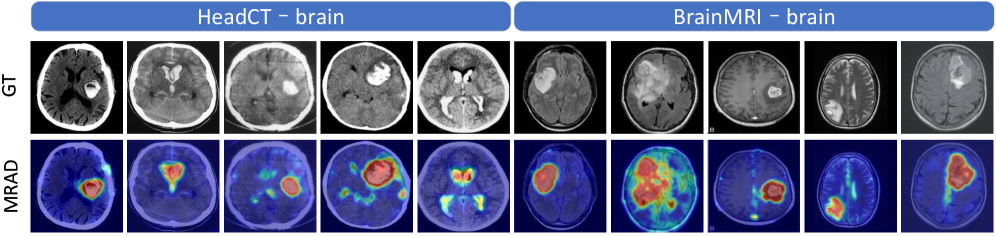

Refer to caption

Figure 4: Comparison of anomaly segmentation results between MRAD-CLIP and other methods.

Qualitative Comparison. In industrial datasets (diverse materials, textures, and imaging conditions), MRAD-FT and MRAD-CLIP consistently rank among the top on both image-level and pixel-level metrics. They also exhibit low across-dataset variance and minimal rank fluctuations, indicating robustness to background clutter and fine-grained defects. In medical datasets (large morphological variability and strong domain shift), the same pattern holds: the lightweight metric calibration and prior-guided prompting preserve decision margins and localization quality under cross-domain transfer. Figure 4 visualizes anomaly maps from both industrial and medical datasets. Qualitatively, the resulting heatmaps show fewer background false positives, tighter anomaly boundaries, and smoother localization of large defective regions across domains. These observations mirror the quantitative gains and further support the method’s stability and generalization. A comparison of parameter counts and inference time with other methods is provided in the Appendix C.3. More visualization results are provided in Appendix D.